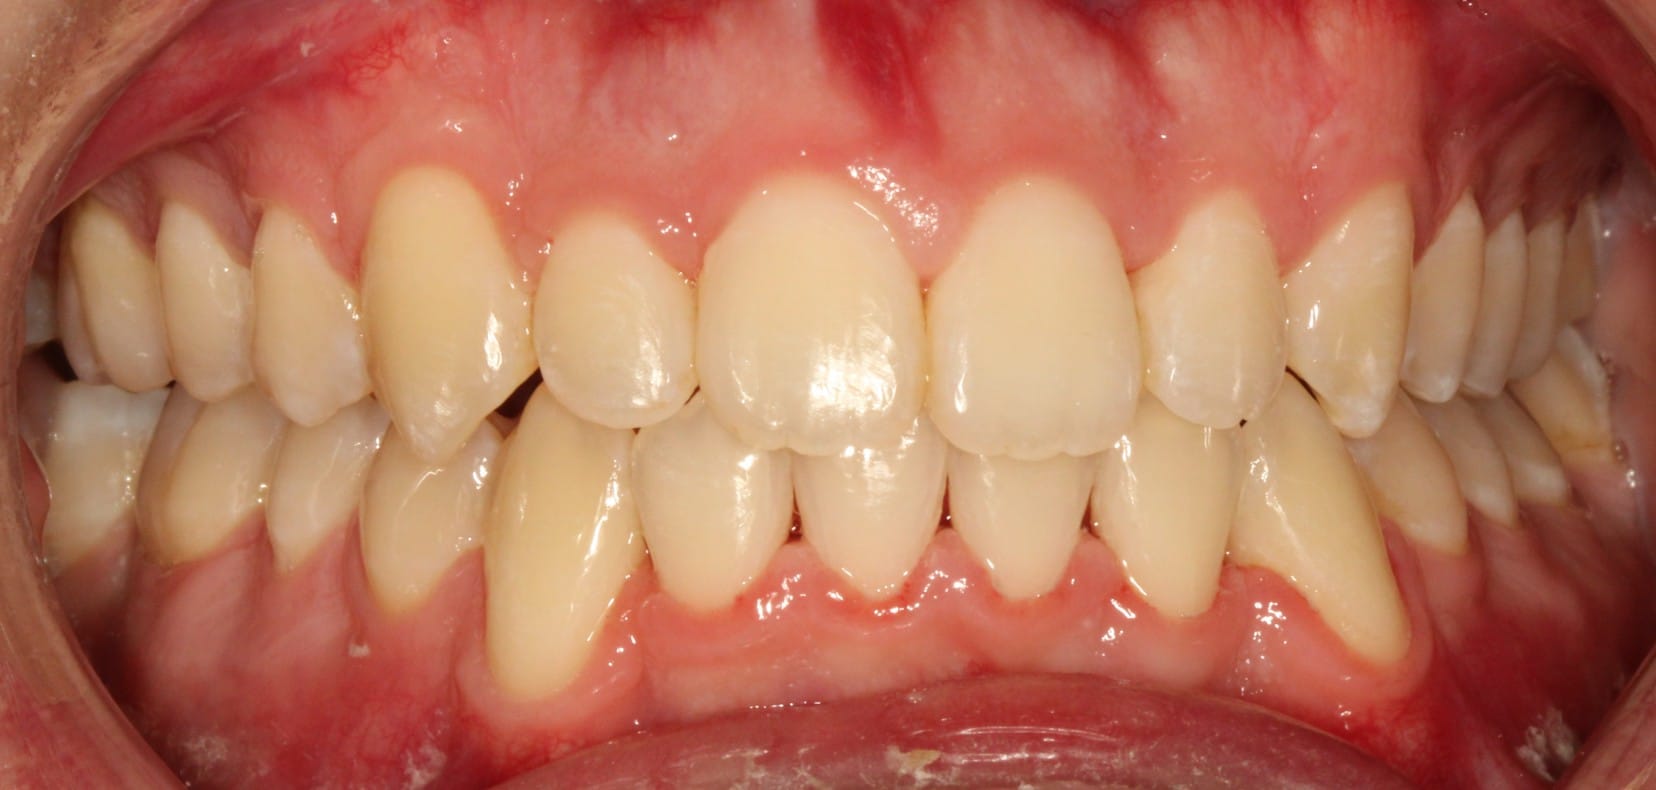

Adult patient treated with Invisalign aligners